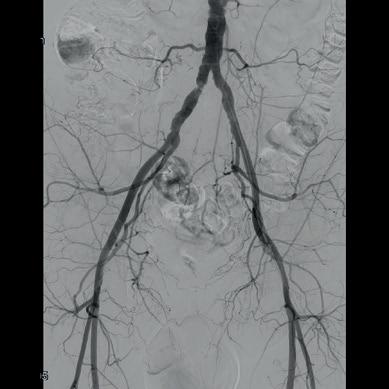

Shockwave intravascular lithotripsy (IVL) “expands endovascular strategies for iliac occlusive disease and can facilitate a ‘leave nothing behind’ approach,” Stefano Fazzini (Tor Vergata University, Rome, Italy) and colleagues write in an open-access Journal of Vascular Surgery (JVS) paper highlighting midterm outcomes from the IVLIAC registry—a multicentre, retrospective study of prospectively collected data.

“CALCIUM REMAINS A CHALLENGE IN the endovascular treatment of iliac artery disease, affecting both procedural and long-term outcomes,” Fazzini tells Vascular News. He goes on to comment that the standard approach of primary stenting, “although effective, is susceptible to stent recoil and under expansion in heavily calcified vessels” and notes that extensive calcification increases the risk of ruptures, especially when high-pressure balloons or balloon-expandable stents are used.

Fazzini also stresses that “no single stent is ideal for all calcified iliac lesions,” and that unnecessary stenting, especially at the bifurcation or when covering key branches, “can be avoided”.

In light of this, Fazzini et al set out to evaluate the midterm outcomes of patients with calcified iliac lesions treated with IVL, with or without adjunctive stenting, and to propose a new algorithm guiding these different treatment strategies.

The new algorithm, Fazzini explains, is based on lesion type (stenosis versus chronic total occlusion) and intraoperative functional assessments (extravascular ultrasound and pressure gradient) to determine whether stenting is necessary. “The impact

of sonic pressure waves improves vessel compliance and luminal gain, but such modifications may not always be evident on digital subtraction angiography alone,” he says, adding that intraoperative functional assessments play a “crucial” role in determining whether IVL alone is enough.

The investigators included all consecutive patients at four centres (Rome, Milan, Negrar and Trento) who underwent treatment with the Shockwave Medical peripheral IVL system for calcified iliac arteries from February 2021 to May 2024. Indication for IVL was Rutherford category of three or above in iliac lesions with moderate-to-severe calcification and was based on the new algorithm. The primary endpoint was primary patency, with assisted primary patency, secondary patency, and freedom from iliac complications also analysed.

Fazzini and colleagues share in JVS that a total of 100 iliac arteries were treated in 86 patients. They note that chronic limb-threatening ischaemia (CLTI) was present in 55% of patients, mean target lesion length was 40.95±29.25mm with a mean stenosis of 84±10%, and 12 of the lesions were chronic total occlusions. The authors report that technical

success was 99% and that target lesions were treated with IVL alone in 77% of cases, whereas IVL plus adjunctive stenting was employed in the remaining 23% of the cases. They add that provisional stenting was performed in 11% of cases, while planned stenting was performed in 12%, and that mean residual stenosis was 14.95±14% at final angiogram. Primary patency and assisted primary patency at 24 months were 95% and 98%, respectively, while secondary patency was 100%. Primary patency showed no statistically significant difference between the IVL only and IVL plus adjunctive stenting groups.

“Shockwave IVL offers a safe and effective treatment option for calcific iliac occlusive disease,” the authors write in their conclusion. “This multicentre experience shows promising midterm results in terms of primary patency despite the very low stenting rate, preserving future treatment options.” They go on to stress that further studies are needed to confirm these findings.

Discussing the findings with Vascular News, Fazzini summarises that, in cases of severely calcified disease, “Shockwave IVL as a first-line strategy in iliac interventions allows for either the avoidance of unnecessary stenting or optimisation of stent expansion, both of which contribute to favourable midterm outcomes”.